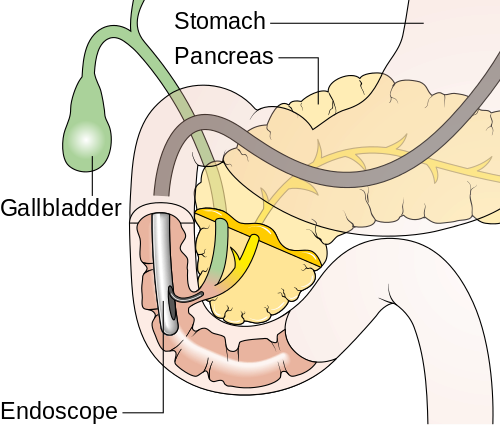

4. Endoscopic Retrograde Cholangiopancreatography (ERCP)

- ERCP is used for both diagnostic and therapeutic purposes, allowing ductal visualization, cytologic sampling, and stent placement for biliary obstruction.

- In select cases, peroral digital cholangioscopy enables real-time visualization and targeted biopsies, improving diagnostic yield for biliary strictures and intraductal lesions.